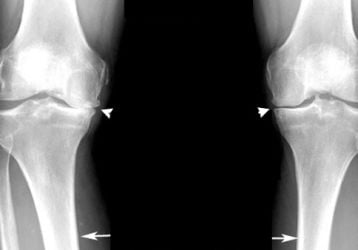

Современный подход к лечению хондромаляции коленного сустава

Что такое хондромаляция коленного сустава. Способы диагностики и и лечения. Список медикаментов и хирургических методов терапии.